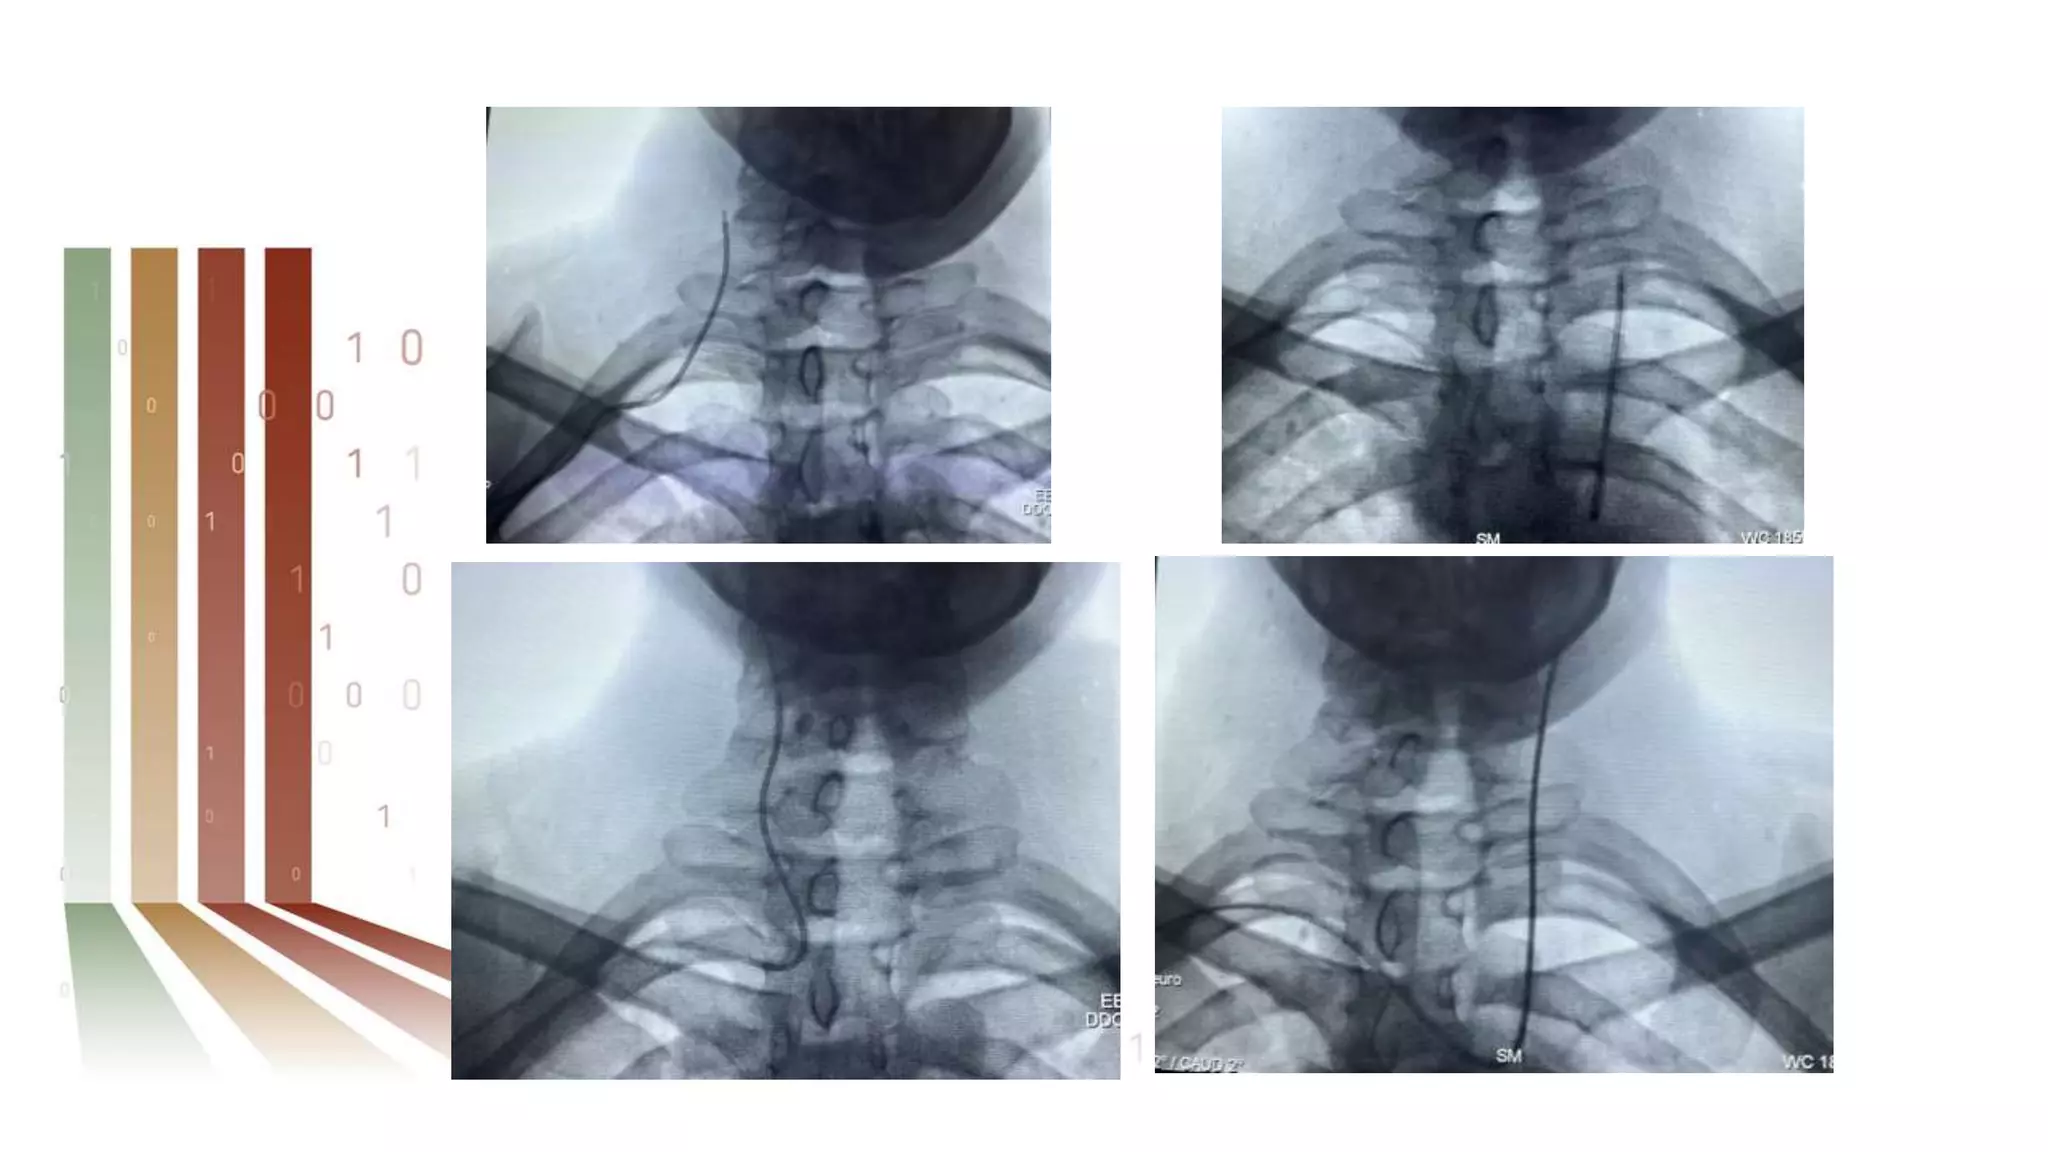

Variations in RA and aorto-subclavian anatomy may

pose a challenge to wire navigation and catheter

manipulation during TRA angiography and

increase procedural time.

If the hydrophilic wire does not traverse the upper

extremity vasculature easily, a 0.014-in wire may

be used under fluoroscopic guidance with a

subsequent exchange for a 0.035-in wire.

RA loops may straighten with wire exchange or by

gently pulling back the catheter with

counterclockwise torque.

Attempts to straighten a 360° loop, however, may

be futile and often are associated with patient

discomfort and greater radiation exposure and

contrast volume.